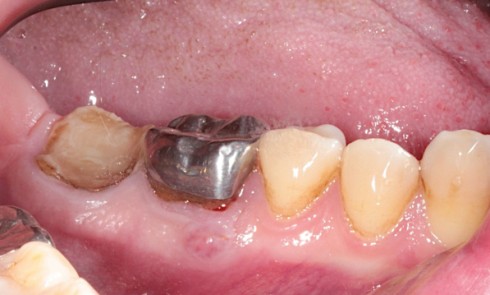

On ne retrouve pas de lésions cutanées faciales. L’examen endobuccal (fig. 1a et b) révèle des plaques jugales bilatérales d’aspect...

Motif de la consultation. Patient de 55 ans venu consulter pour une gêne oropharyngée isolée. Histoire de la maladie. Persistance...